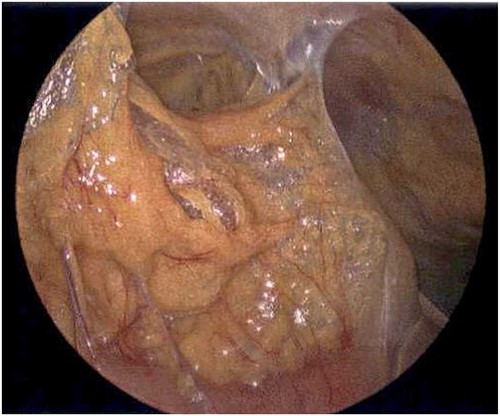

On Hospital Day 2, an interval CXR showed continued resolution of the right-sided pneumothorax but worsening subcutaneous emphysema of the bilateral chest wall and pneumoperitoneum (Fig. 3). Surgical consultation was sought, leading to diagnostic laparoscopy. In the abdomen, emphysematous changes within the gastrohepatic ligament and omental adhesions to the anterior abdominal wall were visualized (Figs 5 and 6). Laparoscopic exploration revealed no diaphragmatic injury or perforated viscera but identified emphysematous changes throughout the preperitoneal space, small and large bowel mesentery, and right paracolic gutter (Figs 7 and 8). Immediate post-op CXR no longer showed evidence of pneumoperitoneum (Fig. 4). The patient was transferred back to the ICU and extubated after three days on Day 5. After the removal of chest tube and transfer to a medical floor on Day 8, the patient developed aspiration pneumonia that was treated with antibiotics. She was discharged on Day 15.

Laparoscope of the large bowel revealing subserosal emphysema within the adventitia.